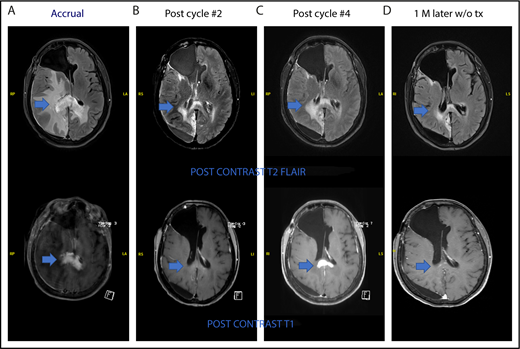

One patient had stable disease after 2 cycles and developed radiologic progression on brain MRI after 4 cycles without any significant clinical deterioration. She was taken off the study as per protocol. Brain MRI 1 month later without steroid or any other treatment showed improvement (Figure 4). This appears to be a case of pseudoprogression. She went on to have treatment with single-agent ibrutinib followed by ASCT and is currently in complete remission.

Pseudoprogression in a PCNSL patient treated with pomalidomide. (A-B) The patient had stable disease after cycle 2 and (C) showed radiologic findings suggestive of progression of disease on restaging MRI of brain after cycle 4 without clinical deterioration. She was taken off study as per protocol. (D) Repeat MRI of brain 1 month later without any steroid or any other treatment showed radiologic improvement. This case is the patient 11 on Figure 2.

We report the first apparent case of pseudoprogression/tumor flare in PCNSL related to IMiD. Although this was not confirmed by biopsy, the subsequent improvement on neuroimaging without steroid or any other treatment was consistent with this diagnosis. The possibility of pseudoprogression now needs to be considered in PCNSL patients after receiving IMiD. Future studies of immunotherapeutic agents such as IMiDs or checkpoint inhibitors should include option for continuation of treatment in these patients who are asymptomatic for additional 1 to 2 cycles before ascertaining true progression. Tumor flare has been previously reported in chronic lymphocytic leukemia and mantle cell lymphoma associated with lenalidomide.27,28